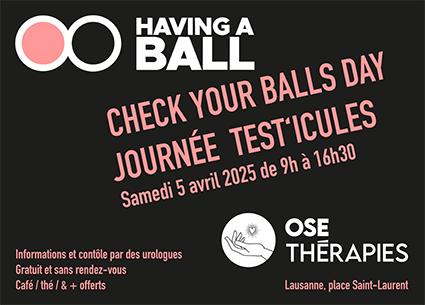

05. APRIL 2025

Check Your Balls Day / Eier-Check Tag

Kostenlose Untersuchungen durch einen Urologen des CHUV auf dem Place St-Laurent. Diese Veranstaltung wird in Zusammenarbeit mit OSE Thérapies im Rahmen des April als Monat der Sensibilisierung für Hodenkrebs.